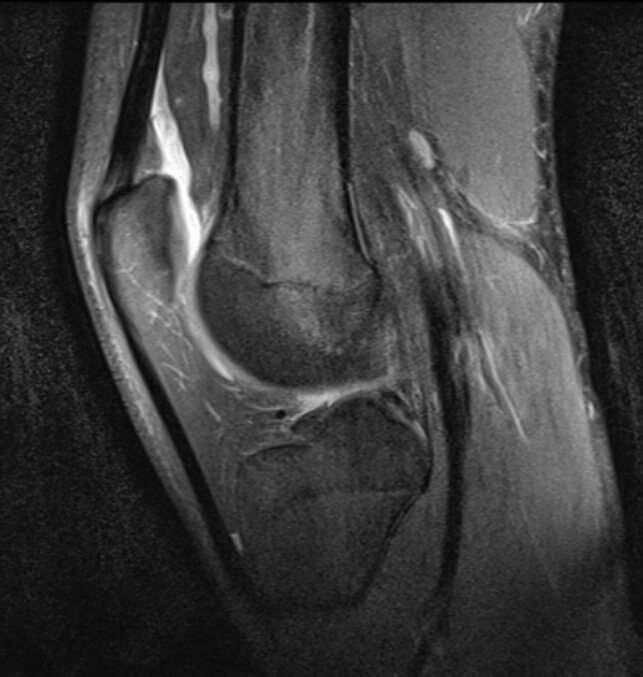

- Хорошая визуализация мягких тканей (мышцы, сухожилия, связки, хрящевая, нервная ткань);

- Возможность оценить трабекулярный отек (с точки зрения своей специальности выношу это в отдельный плюс);